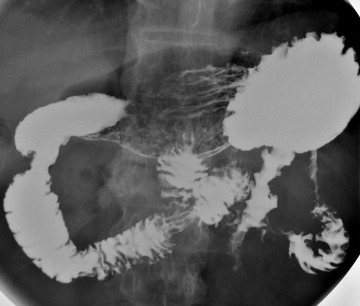

위조영술 검사는 바륨이라는 하얀 액체를 마시고 그 액체가 식도를 타고 내려가면서 위에 쌓였을 때 몸을 이리저리 뒤집어가면서 그 흑백화면을 보면서 읽어내는 검사방법입니다.

바륨현탁액, 요오드제제를 이용해 위의 이상 유무를 검사합니다. 이 용액은 X선 투과가 잘 안되는 물질로 이 용액을 마시고 X선이 발생되는 기계 위에서 몸을 이리저리 돌려가면서 검사를 받습니다. 기계가 알아서 돌아가는 것이 아니라 사람이 직접 그 기계 위해서 몸을 움직여 줘야 합니다.

X선이 발생하는 기계 위에 있으므로 그 방사선이 몸을 투과하므로 미량의 방사선 피폭이 있다는 것은 인지해야 합니다. 위조영술 검사방법은 위를 풍선처럼 팽창시켜 위벽에 조영제 코팅해 위벽 병변 유무를 검사하는 방법과 위가 팽창하지 않은 상태에서 위를 조영제로 채워 검사하는 두가지 방법이 있으며 일반적으로 두가지 다 시행해야 위벽과 안을 다 검사 할 수 있습니다.

하지만 위조영술 검사 장점도 분명히 존재합니다. 이는 그래도 위내시경 검사처럼 굵은 카메라를 삼켜야 하는 불편함이 없으며 노인이나 기저질환이 있는 환자도 위 검사를 받을 수 있고 식도에서 위 그리고 십이지장으로 이어지는 위장관의 전체적 모양과 연동운동을 관찰 할 수 있다는 점입니다.